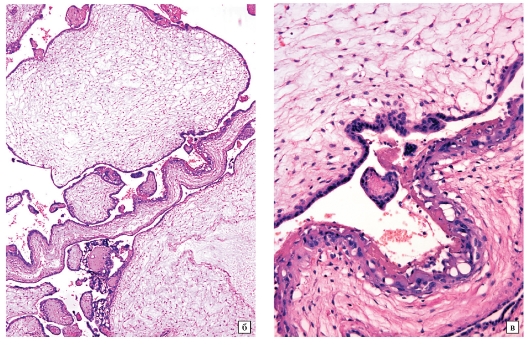

а - Микропрепарат частичного пузырного заноса при небольшом увеличении: увеличенные ворсины плаценты с отеком стромы, неровность краев ворсин и трофобластические включения в их строме.

Пролиферация трофобласта минимальная

б - Микропрепарат ворсин частичного пузырного заноса при большом увеличении:

в строме мелкие сосуды, содержащие эритроциты плода с ядрами